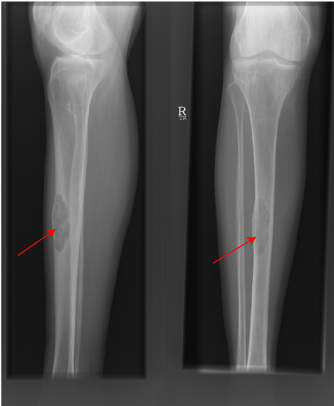

Brown Tumour of Tibia due to hyperparathyroidism

Primary hyperparathyroidism (pHPT) is the inappropriate excess production of parathyroid hormone. The term hyperparathyroidism was first coined in the 1920s to describe a syndrome characterised by bone disease, renal stones, fatigue, hypercalcaemia and high urine calcium. The diagnosis was dependent on symptoms related to “bones, stones, abdominal groans and moans” which often correlated with severe bone disease, advanced kidney disease, psychiatric and neuromuscular disorders respectively. The symptoms were often associated with evidence of calcification of the kidneys, bone erosion of the fingers, boney tumours and changes in the appearance of the skull on Xray.